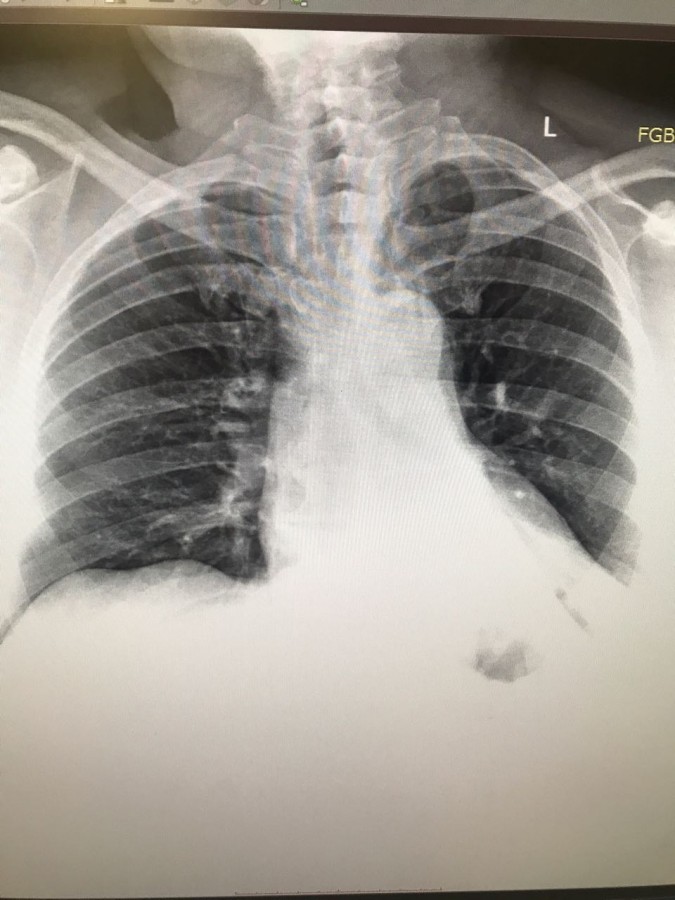

На рентгене гиповентиляция - признак центрального рака

Обсуждалось в Госпитале Ослабленных Сердец